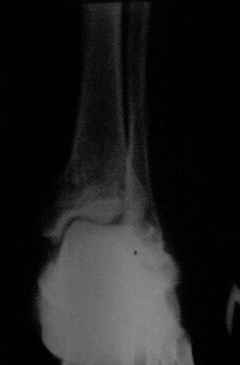

Отправляю снимки(свежие)и фото стоп.

С уважениемД.Б.

С левой стопой дело похуже. Нужен прямой снимок, да и боковой не помешает повторить на всю стопу, ну и плюс аксиальный. Готовтье аппарат.

Присоединяюсь к мнению Я.Одесского о необходимости аксиальных снимков и, наверное, сразу снимков по Бродену (через каждые 10 градусов внутренней ротации стопы). Кроме этого необходима КТ. Она позволит уточнить срослись переломы или нет. Соответственно и тактика: если не срослись можно попробовать АВФ; если срослись -артродез.